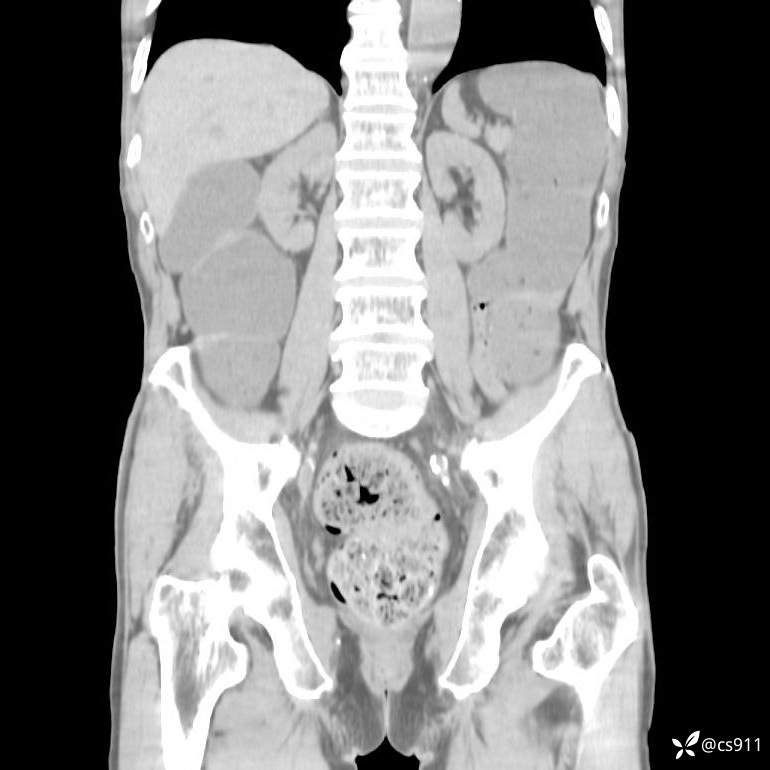

急腹症之急诊CT,原因?答案公布

男,77岁,腹痛、腹胀伴恶心呕吐1天。呕吐胃内容物,非喷射性呕吐,有咖啡色样胃内容物,诉有胃穿孔病史。查体:全腹平,下腹部压痛,全腹无反跳痛,叩诊呈浊音,移动性浊音阴性,肠鸣音减弱,1-2次/分。肛检:直肠未扪及明显肿物,可触及大量粪块。

T 36.6℃ P 80次/分 R 26次/分 BP 100/60mmHg

白细胞(WBC) H 14.55 10e9/L 4-10

中性粒细胞百分率(NEUT%) H 85.7 % 40-75

血淀粉酶(AMY) HH 1859 U/L 35-135

癌胚抗原(CEA) H 27.44 ng/ml 0-5

呕吐物 潜血试验 * 阳性 阴性

患者轮椅入室检查神志清楚, 能配合摆位和呼吸